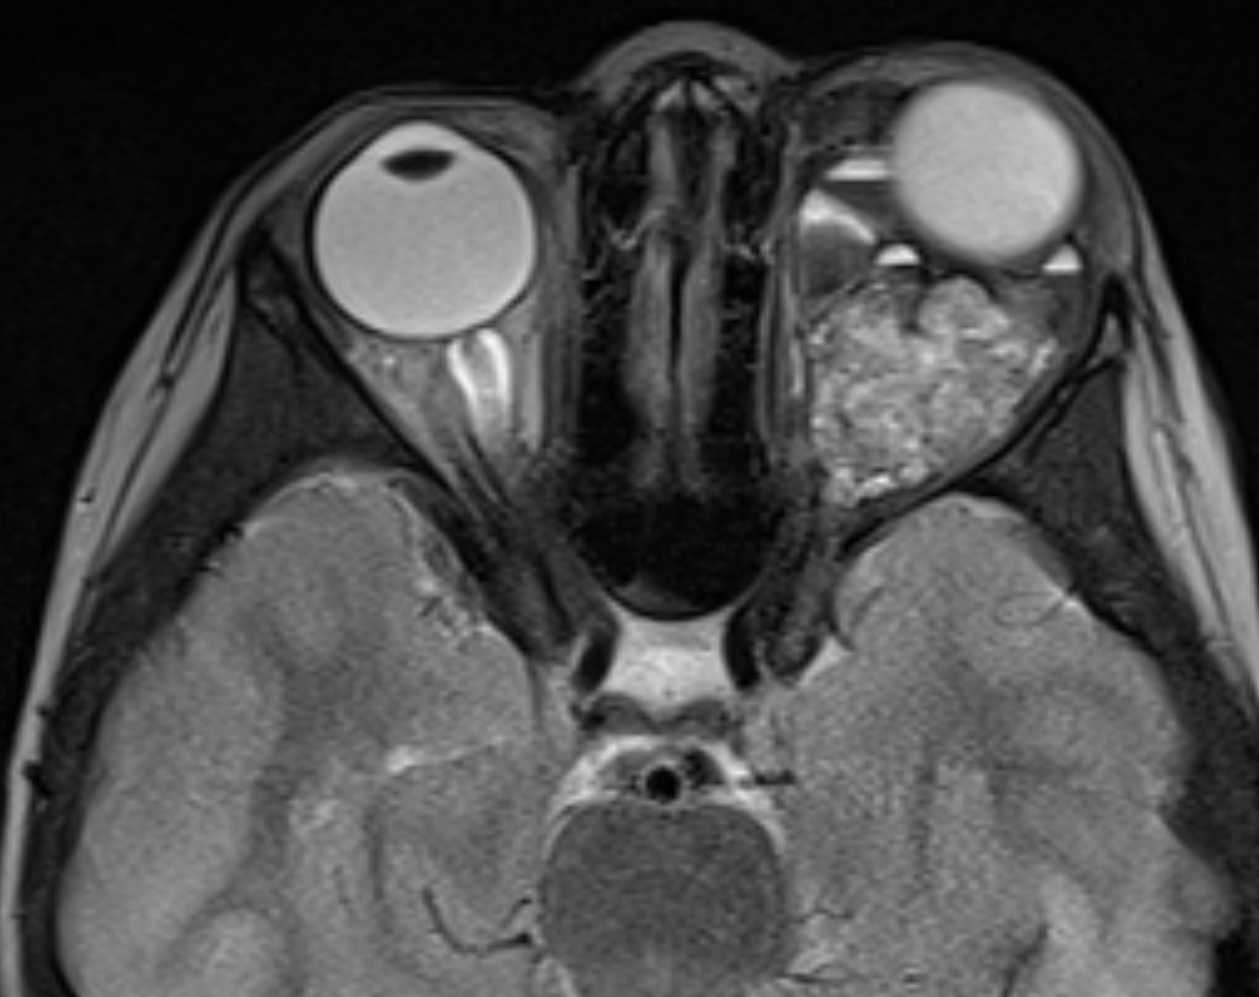

MRI of small LM cysts (top), US of needle injecting individual cysts (left), photo of US guided technique for small cyst puncture (right).